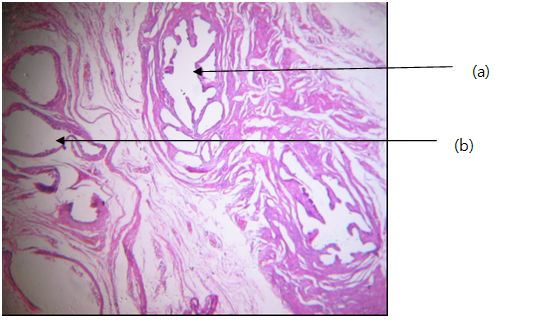

It was an individual who has 15-year-old, declared a female gender at birth. On physical examination, female-type secondary sexual characteristics were normal, including well-developed mammary glands, triangular pubic hairiness, and a regular endometrial cycle since one year before the diagnosis. The external genital tracts, showed sexual ambiguity (Figure 1) with a normal hymen, a vaginal vestibule, small and large hypotrophy lips, and a hypertrophy clitoris taking the appearance of a penis measuring 2.5cm. The labioscrotal (para-clitoral) region contained a scrotum within which an ovoid, mobile mass, the size of a normal testicle, was palpated. For the internal genital tracts, pelvic ultrasound showed a deviated uterus on the left and a left ovary, both normal. Surgery was decided and consisted of excision of the intrascotal mass, followed by vaginoplasty and enlargement associated with a clitoral reduction plasty (Figure 2). Macroscopically, the mass looked like a normal testicle capped by the epididymis (Figure 3). On histological examination (Figure 4), coexistence of ovarian parenchyma with ovarian follicles at different stages of maturation, and testicular with seminiferous tubules associated with hyperplastic Leydig cells were observed. Both parenchymas are separated by a connective thin stroma. Epididymal and vas deferens ducts were normal (Figure 5). Following treatment consisted of a vaginal calibration with candles every week after the healing of the surgical wound. The patient was lost sight of after 3 calibration sessions.

Figure 4 Ovary and testicular parenchyma. 100x.

1. Seminiferous tubes

2. Ovary parenchyma.